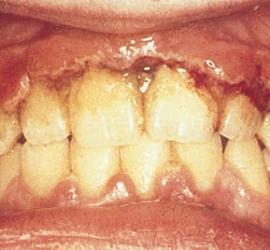

Ретроградный кариес. Кариозный процесс разрушает дентин со стороны пульпы. Наблюдается при наличии интактной, кариозной и пломбированной коронки, а также в случае гангрены пульпы кариозного и травматического происхождения. Со стороны полости пульпы идет процесс распада дентина за счет функции микроорганизмов и протеолитических ферментов. Ретроградный кариес может иметь место при хроническом пролиферативном […]